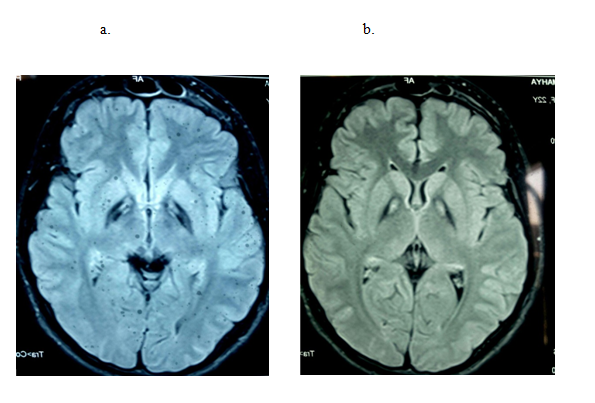

We report an 7-years-old Iranian female present from nonconsanguineous marriage, with history of normal birth and milestones, no history of seizure, with gait disturbance presented at 4 years of age, starting from lower extremity stiffness and frequent falls while walking. Her disease followed by spasticity in the upper extremity. The disease gradually progressed with dysarthria, dysphagia and drooling. Over next year, she had abnormal episodic posturing at oromandibular and then at upper limb, neck, lower limbs, and sometimes trunk follow by generalized dystonia. She had not any history of visual or cognitive disturbance. The neurologic examination revealed the presence of Parkinsonism feature including masked face, the rigidity of four limbs & axial rigidity, oromandibular and generalized dystonia as well as the presence of hyperreflexia and spasticity of the lower limbs, with flexor plantar reflex. The neuro-ophthalmologic exam, including fundoscopy excluded retinitis pigmentosa and Kayser-Fleischer ring. The examination also revealed mild cognitive impairment with mini mental status examination (MMSE). Her laboratory workup included normal serum copper, ceruloplasmin, and ferrit in levels and no acanthocytes were found on a blood smear. Brain MRI shows bilateral symmetrical T2 weighted hypo intensity in the globus pallidus with central hyper intensity, suggestive of typical 'Eye of Tiger' sign (Figure 1). She was homozygous for PKAN2 mutation and finally, the classical PKAN was diagnosed. She is now under symptomatic treatment with Botulinum Toxin A and trihexyphenidyl

Figure 1 (a) Axial SWI weighted, (b) fluid attenuation inversion recovery MRI showing low signal intensity in the bilateral globus pallidus with a medial area of signal intensity, presenting the classic “eye-of-the-tiger” sign.